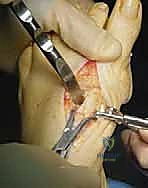

TECH FIG 1 • A. The adductor hallucis tendon is released off the proximal phalanx and fibula sesamoid. The suspensory ligaments of the fibula sesamoid are released. B. Medial capsulotomy and exostectomy.

TECH FIG 2 • A. The web space incision is extended proximally in a lazy-S shape toward the base of the first metatarsal. The extensor hallucis brevis is identified and protected. B. The first tarsometatarsal joint is localized to define the limit of the cut.

- Deepen Dissection: "Continue to deepen your dissection through the interval between the EHB and EHL, using our small pointed retractors to expose the dorsal and lateral aspects of the first metatarsal base. Ensure you have clear visualization of the entire area where the osteotomy will be performed."

TECH FIG 3 • A. Compression with the clamp “greensticks” the medial cortex. B, C. Two screws are inserted in a lag screw fashion. D. The capsule is repaired. The skin is closed.